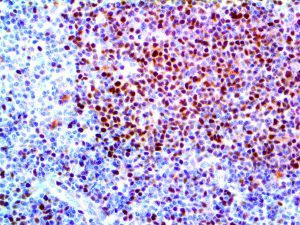

It is the ICU physician who is most likely to witness one of the deadliest manifestations of the abnormal immunological response, the cytokine storm syndrome (CSS). This response is also referred to by some as the cytokine release syndrome (CRS). CSS is characterized by continuous activation and expansion of macrophage and lymphocyte populations, which secrete large amounts of cytokines, causing the cytokine storm. This massive cytokine release is akin to hemophagocytic lymphohistiocytosis (HLH) disease, a syndrome characterized by initial unchecked and persistent activation of cytotoxic T lymphocytes and NK cells.

Clinical and laboratory manifestations of HLH include fever, enlarged liver and/or spleen, neurologic dysfunction, coagulopathy, liver dysfunction, cytopenias (i.e., low levels of erythrocytes, leukocytes, and/or platelets), hypertriglyceridemia, hyperferritinemia, hemophagocytosis, and eventually diminished NK cell activity as the immune system becomes progressively paralyzed. HLH can be familial (primary HLH) or secondary to another disease process (sHLH), such as rheumatic disease, in which it is referred to as macrophage activation syndrome (MAS, characterized by elevated ferritin).